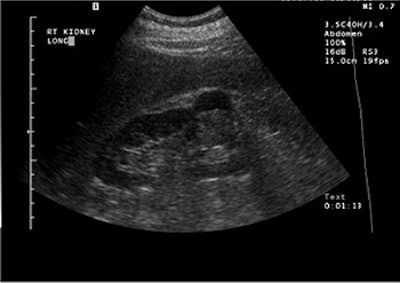

"Ultrasound with contrast has advanced over the years," Barr said. "We now have as many sequences ... as there are in MRI." At the time of these studies, the level of ultrasound technology that his group was using allowed them to inject contrast into a large renal cell carcinoma, and pick out the individual vessels in the cell. Also, the mass enhanced more than the normal renal cortex on ultrasound.

A large renal cell carcinoma on pre-contrast ultrasound (above). After injection of the contrast agents (below), there is enhancement. Individual vessels in this renal cell carcinoma can be picked out; the mass also is enhancing more than the normal renal cortex. "If we increase the mechanical index, we can actually eliminate most of the parenchymal phase and actually look at discrete vessels," Barr said. Images courtesy of Dr. Richard Barr, Ph.D.